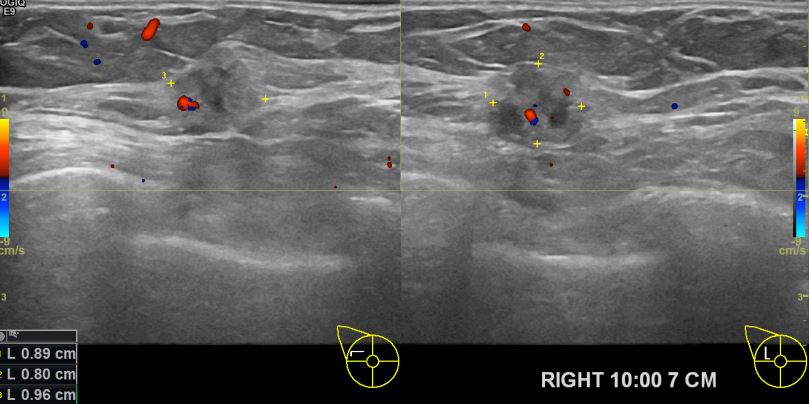

상기환자 건강검진상 이상소견있어 조직검사권유 받아 내원하신 60대 여성분으로

의심스러운 우측 유방멍울 조직검사후 유방암 진단되셨읍니다.빠른 쾌유를 바랍니다